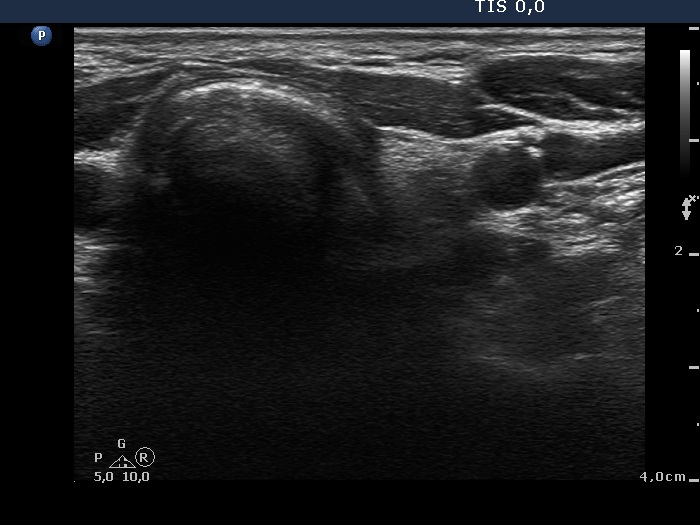

Ultrasound. Connective tissue replaced the thyroid parenchyma in both thyroid beds. There were tiny hypoechoic areas in the right thyroid bed. Two larger hypoechoic lesions were found, one in the isthmus and the other in the left thyroid bed. The latter presented vascularity.

Comment. The presentations of the hypoechoic lesion in all three sites were the same, they differed only in their size. Naturally, the two larger in the isthmus and in the left thyroid bed could cause and did cause concern. Especially that in the left lobe due to its intralesional vascularity. The larger lesions can correspond to small muscle fibers, remnant of the regenerative provess after the surgery but even damaged, non-viable thyroid tissue. Taking the thyroglobulin level into account, the risk of thyroid cancer is minimal but not zero.